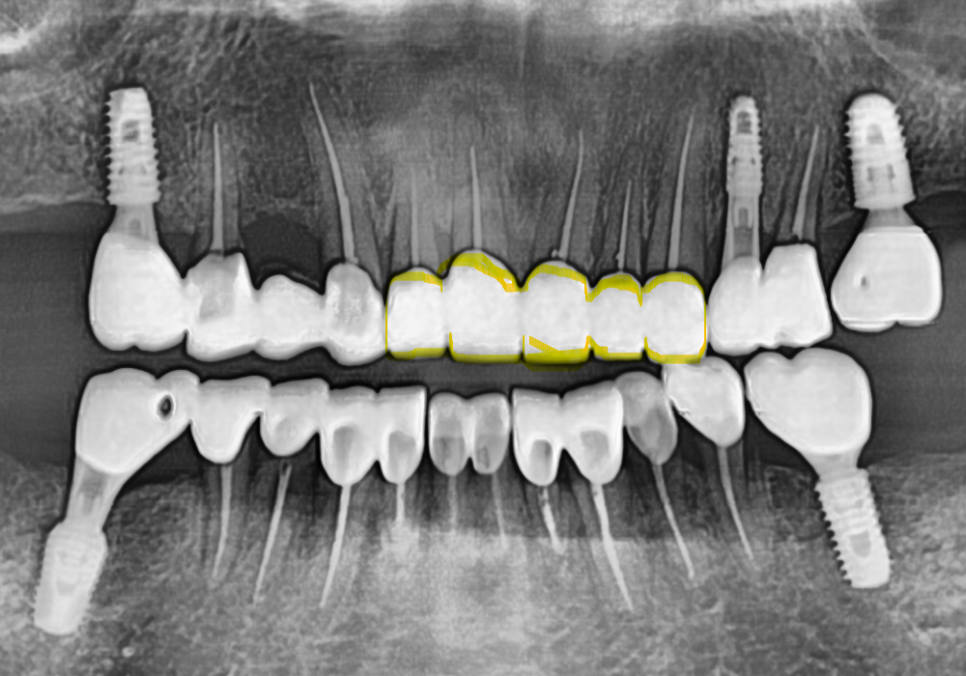

환자분의 연세를 고려하여 무리가 되지 않도록

상악부터 순차적으로 치료를 이어갔습니다.

각 부위당 신경치료를

꼼꼼하게 마무리한 뒤

임시 치아를 거쳐

최종 보철물을 제작했습니다.

보철물을 올릴 때는

음식물이 최대한 끼지 않도록

정밀하게 설계하는 데 집중했습니다.